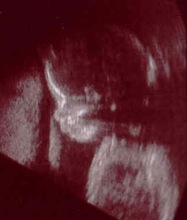

Carlynn and I actually picked out Stephanie's name twenty years ago when we were musing about our future children. We have prayed for the arrival of our children during years of infertility. After fifteen years of marriage we were still praying that God would give us a daughter. And after almost three years of trying to conceive, Stephanie was a reality.

God created this life and it will be up to him when he chooses to take it. If Carlynn's womb is the only home she ever knows, we are committed to making it as safe as possible and free from the intrusion of the abortionist's tools.

My Mom & Dad wrote this before I was born as a public response to those who suggested that they abort me because of my diagnosed disabilities.